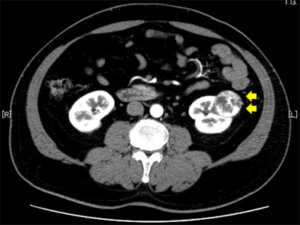

RCC と診断された人の多くは、別の理由で検査を受けた後に診断を受けます。症状が出る前に、超音波検査やCTスキャンで腫瘍が見つかることがあります。

塊

RCC によって引き起こされる腎臓腫瘍が非常に大きくなると、体の外側に広がる、または触ることができる目立つしこりが生じることがあります。しこりは通常、腹部の低い位置、背中、胸郭の下、または脇腹にあります。このようなしこりを作るには、腫瘍がかなり大きくなければなりません。